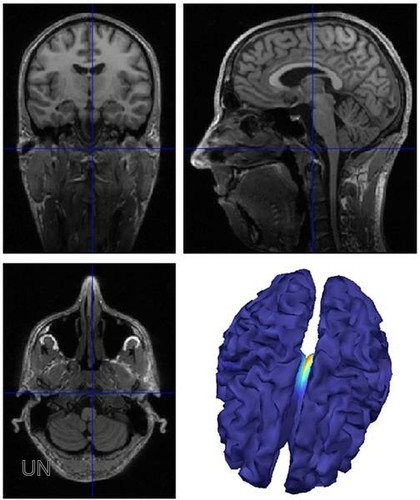

Cientificos Argentinos identifican un mecanismo que causa la epilepsia y la resistencia a la medicación

El hallazgo de científicos de la UBA permitiría en el futuro prevenir convulsiones y ayudar al 30 por ciento de los pacientes que no responden a la medicación convencional Nuevo método no invasivo para detectar...